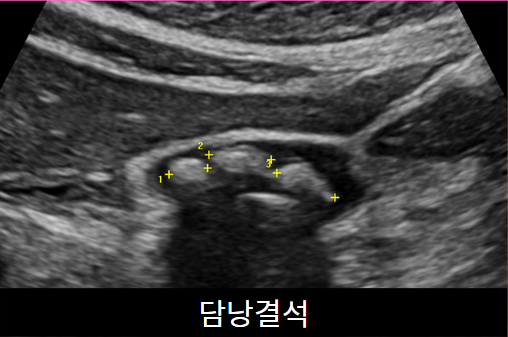

상복부초음파(간,담낭,담관,췌장,비장)

가장 많이 하는 초음파입니다. 간,담낭, 총담관, 췌장, 비장, 신장을 검사합니다. 지방간, 간경화, 간암, 혈관종, 담낭돌, 담낭용종, 췌장염 등을 진단할 수 있습니다.  약 10분 정도 소요되며 다른 검사와 달리 8시간의 공복이 필요합니다.